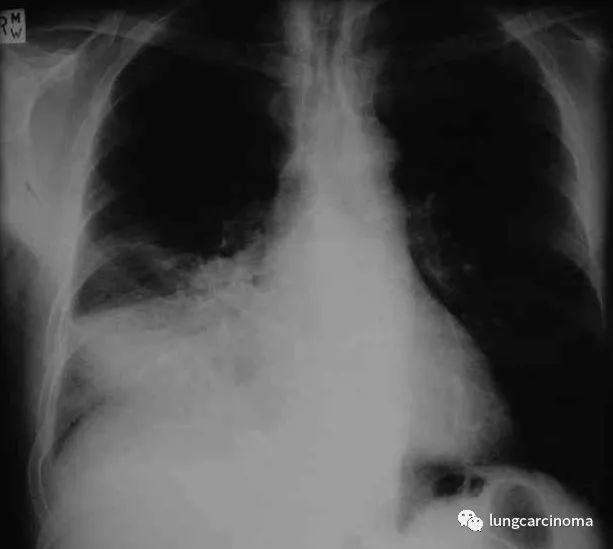

在此期间,在这些高血压患者中

确诊了7,952例肺癌

(每1000人中1.3例/年)。